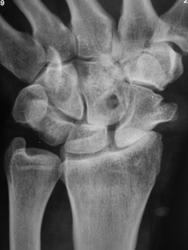

Пациент направлен хирургом на рентгенографию лучезапястного сустава с дежурным диагнозом – «ДОА».

ДОА, экзостоз ладьевидной и "непонятное" в головчатой, может остеоидная?

похоже и подвывих имеется...

Интересно консолидированный перелом ладьевидной, остеоартроз неинтересный. А вот дырочки в метафизе луча и в центре головчатой - уже гораздо интереснее. Предположу остеоид-остеому и искуственное происхождение, соответственно.

Ночью суставы болят у очень многих - и при ДОА, и при Бехтерева, и при ревматоидных делах, это - не показатель. Я бы отметила сквозное отверстие головчатой кости (да-да, прямо так в протоколе), конс.пер.ладьи, остеоид-остеому луча, остеоартроз и направила бы к хирургу обратно.

А может, то, не перелом ладьи, вон коллега написал "экзостоз", а может остеохондрома?

Дырочка аккуратная. И впрямь, как искусственная. Вот бы ее почетче вывести в боковой проекции - если круглая, а не тунелем, значит киста, а не "экзогенная". Дисконгруэгтность ладьи, головчатой и полулунной. Луч невнятен, хотя и на томо - с участком разрежения без четких границ и плотным включением. А вот на первой обзорке хорошо видня хрящевая шапочка экзостоза ладьи.

Кортекс луча странный, как вдавлен внутрь. Может быть: травма-кровоизлияние-оссификация гематомы. Для остеоида внешний контур нечеток. На остеомиелит тоже не похоже.

Ростом хрящевой шапочки экзостоза, видимо, объясняется смещение ладьевидной кости и последующее формирование артроза II-III ст. в луче-ладьевидном и полулунно-головчатом суставах. В метафизе луча ничего стоящего внимания. А «дырка» может быть интересна. Хорошо бы боковую томограмму через этот феномен. Или попробовать снять на маммографе с увеличением на предельных 35 kV прямо и косо.